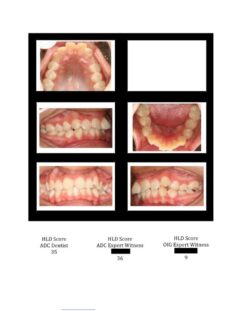

So here again are photos of children’s teeth that were pre-approved for treatment by the state’s Medicaid claims administrator TMHP/ACS, that HHSC-OIG now claims were fraudulently scored by Medicaid dental providers. These cases are from the SOAH hearings that have been completed for Harlingen Family Dentistry and Antoine Dental Center. The SOAH courts found both practices innocent of any allegation of Medicaid fraud or misrepresentation. The photo pages show the attending dentist’s HLD score, the dentist’s expert witness score and the OIG expert’s score.

Antoine Dental Center